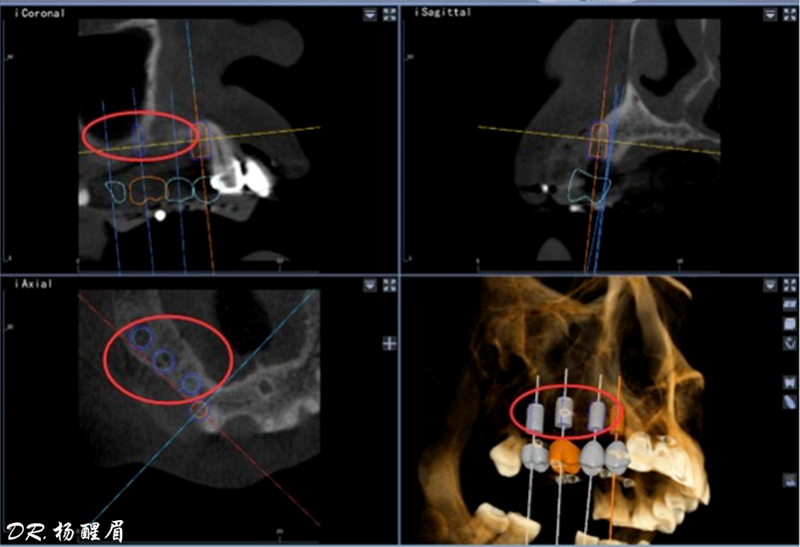

®根據(jù)CBCT中牙冠顯影位置,按照修復引導種植的原則進行方案設計

®使用迪凱爾易植美導航軟件進行方案設計,確定種植體使用方案,以及種植位點,方向和深度

®多顆植體種植方案應盡量保持軸向在同水平線上